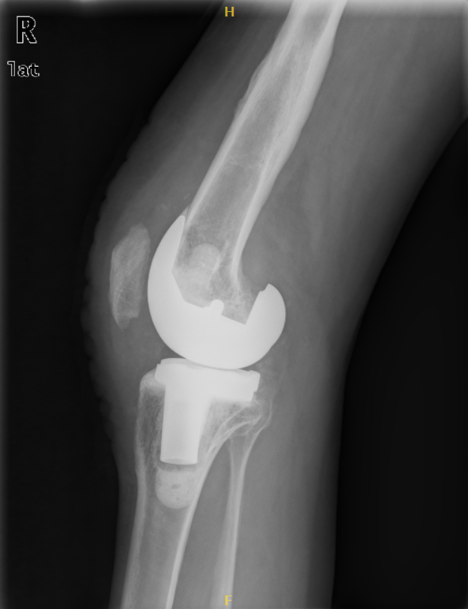

1、术后影像

3、术后3年复查